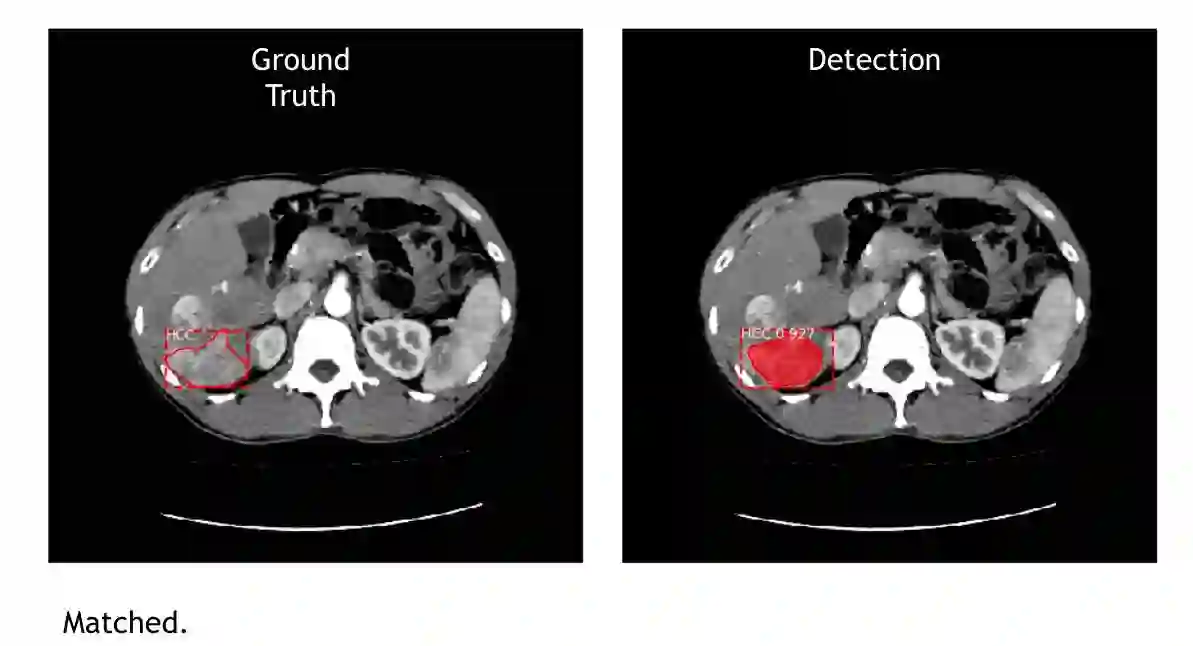

图|左图是医生手动标示,右图是 AI 侦测的结果,机器都能找出肿瘤位置及大小。(图片来源:CMUH人工智能医学诊断中心)

不仅 AI 可以找出肿瘤位置、框出边缘,甚至还出现惊喜,游家鑫指出有两个很特别的状况,一个是他们没有教机器 nodule in nodule 肿瘤中还有一个肿瘤这种低机率低的情况,但它自己找出来了,当初研究人员看到机器标这张图,还以为机器出错,就拿去请教医生,才知道原来这就是 nodule in nodule 。另一个就是有一张素材里有一个“人为标错”的状况,因为有时医生真的太疲累而画错,但机器却自己找出正确的肿瘤位置。

图|这张图就是 nodule in nodule ,他们没有教机器这个状况,但机器自己发现了,不过也值得注意的是,对于第二颗肿瘤机器下判断的自信程度是 HCC 0.8 ,对比一般机器的自信通常都会超过 0.9 来说,它是稍微没有自信,但还是识别出来了。(图片来源:CMUH人工智能医学诊断中心)